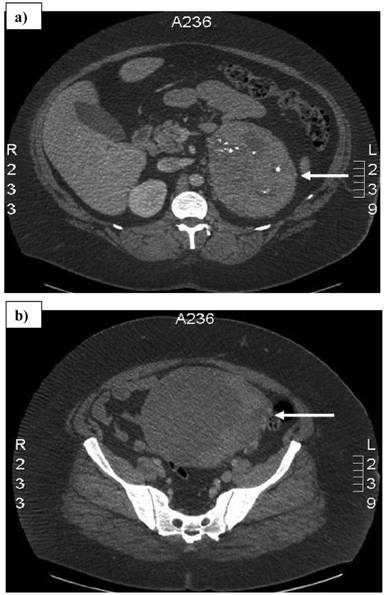

A 32-year-old woman with a history of vaginal bleeding presented to a referring hospital with edema of the left lower extremity. A computer tomography (CT) scan of the pelvis showed a left pelvic mass and a deep venous thrombosis. She underwent a uterine biopsy which revealed a grade I endometrial adenocarcinoma. A staging CT scan demonstrated a heterogeneous central and left pelvic mass measuring 16.8 x 14.8 cm and a 14.5 x 10.7 cm left adrenal mass. (Figure 1) Before she was referred to our institution, a biopsy of the adrenal mass was done to exclude hormonal overproduction and interpreted as consistent with an ACC. Magnetic resonance imaging further delineated the pelvic mass as two separate masses: a 2.3 cm uterine mass and a 15.5 x 15.3 cm left adnexal mass. (Figure 2)

Figure 1

Computed tomography scan showing a) 14.5 x 10.7 cm left adrenal mass with areas of necrosis and internal calcifications, and b) 16.8 x 14.8 cm pelvic mass. Arrows denote the tumors.